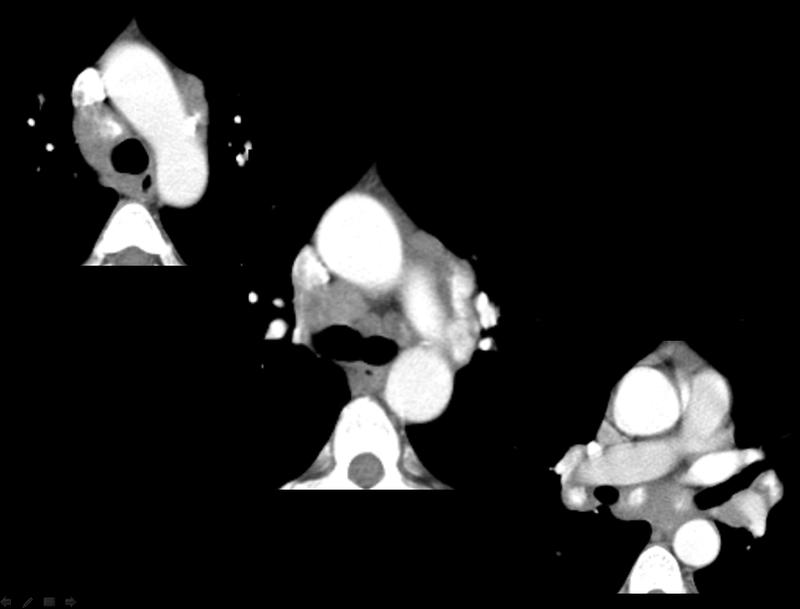

Gallery Sarcoid Sarcoid CT Case 4

Sarcoid CT

Case 4